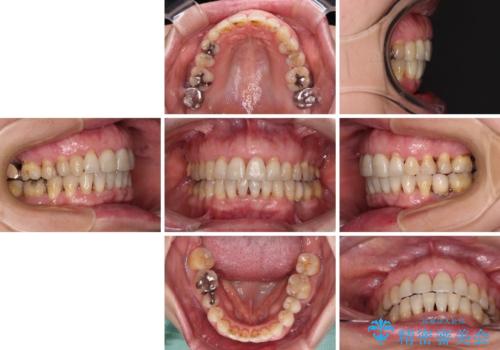

- 近医にてインプラント治療を行った後に矯正治療を希望され、来院された患者様です。

口元の突出感とデコボコが気になっているとのことでしたが、インプラントが既に3本埋入されていたため、抜歯矯正による口元を引っ込めることができない状況でした。

近医での歯周病治療の影響でブラックトライアングルが発現していたため、IPR(歯と歯の間を削る)で隙間を改善しつつ、インプラントを固定源に歯列全体を後方へ移動させることとしました。